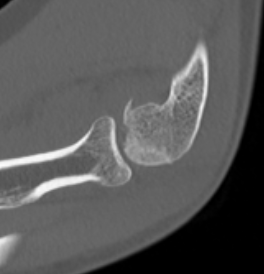

Dubberly Classification

| Type I | Type Ii | Type III |

|

Capitellar fracture

Capitellum + trochlea fracture In one piece Double arc sign seen on xray |

Capitellum + trochlea fractures In two separate pieces |

Double arc sign on xray |